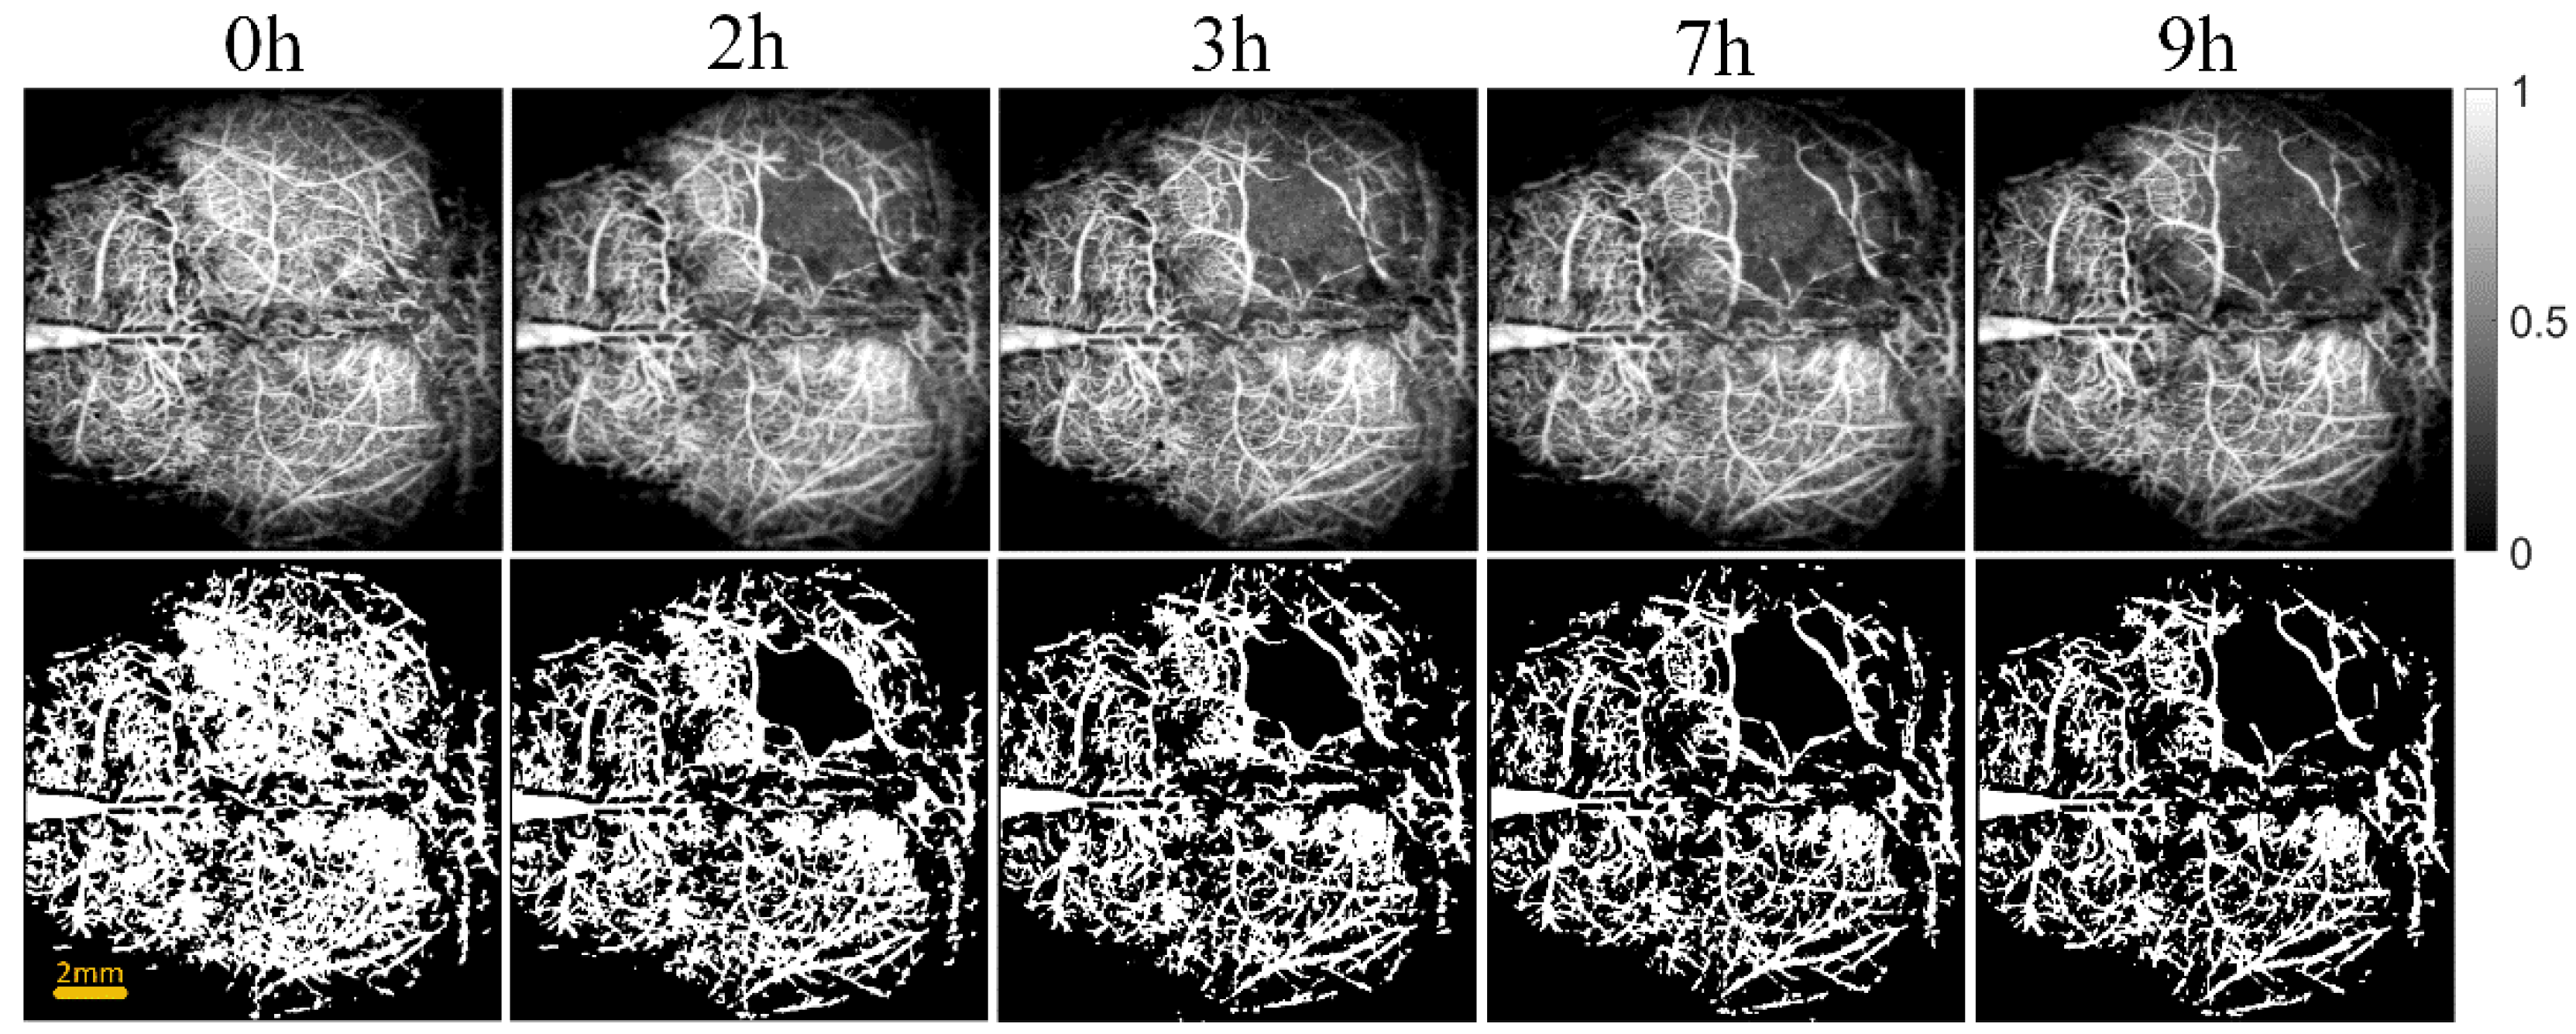

2.2.2. OCT Angiography

2.2.3. Blood Vessels Segmentation